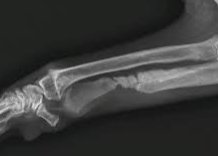

骨髄炎は血行性に、あるいは隣接感染によるものが多く、開放性骨折の場合にも発生します。

化膿性骨髄炎では、骨内に膿瘍abscessが形成される。

もし化膿が著しいか、あるいは膿瘍を形成したものには、切開手術によって膿の排出をはかり、また消毒殺菌剤の溶液がしばしば応用されます。

骨壊疽および壊死が存在する時は、その部分を剔除すべきです。